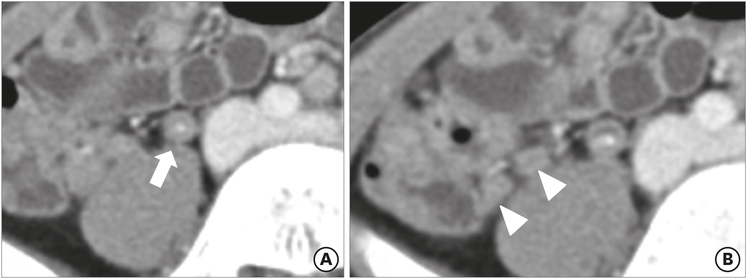

The mean maximal diameter of the appendix was 9.56 mm in the true appendicitis group and 7.28 mm in the negative appendicitis group. According to the definition of appendiceal enlargement (>8 mm in maximal diameter), 3 patients (23.1%) in the negative appendicitis group had an enlarged appendix, while 60 patients (68.2%) in the true appendicitis group had appendiceal enlargement (Fig. 1). This difference was statistically significant (p=0.002). Periappendiceal fat inflammation, or fat stranding, was noted in 2 patients (15.4%) in the negative appendicitis group and 43 patients (48.9%) in the true appendicitis group (p=0.023) (Fig. 2). For the other measured findings, there were no significant differences between the groups. The ACT findings are summarized in Table 2, along with their odds ratios and 95% confidence intervals (CIs).

Fig. 1

Preoperative abdominal computed tomography findings for a 9-year-old male patient, who was demonstrated to have serositis: (A) appendicolith with focal wall thickening (arrow) and (B) adjacent mesenteric lymphadenopathy (arrowheads) were observed, but there was no associated periappendiceal fat infiltration or appendiceal enlargement.